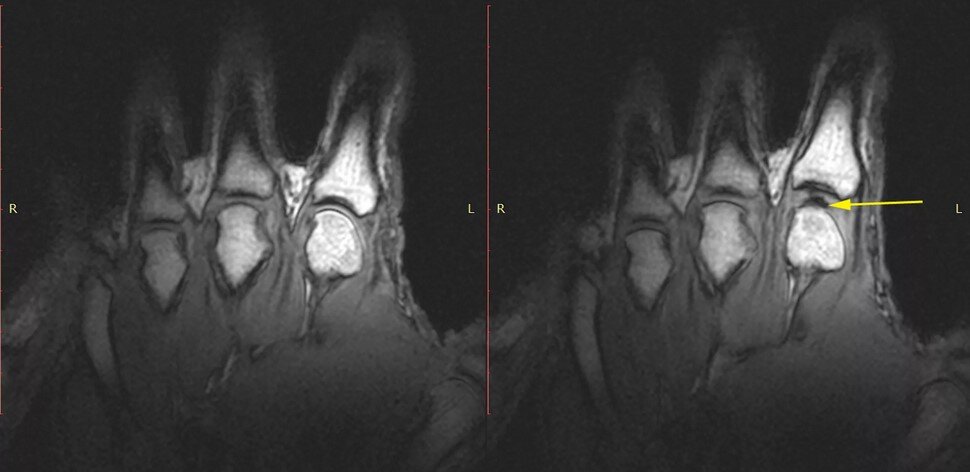

МРТ снимок сустава во время хруста пальцами.

Многие люди думают, что звук хруста издают кости, но это не так. Из-за изменения объема и давления в суставной сумке образуются пузырики газа, которые лопаются и создают звук хруста. Хотя не все ученные согласны с данной теорией. Некоторые из них считают, что звук возникает в момент формирования данных пузыриков газа. Но для нас это не имеет никакого значения.